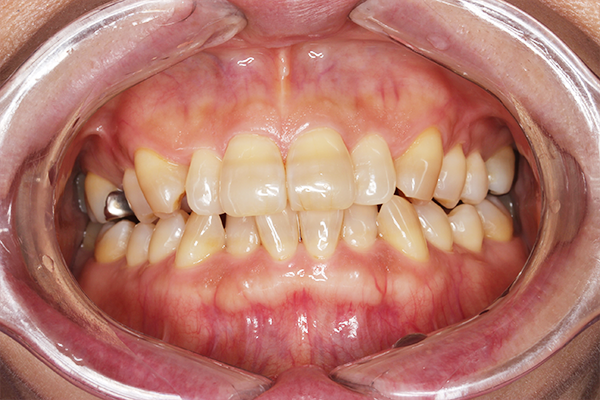

術前

術後

オフィスホワイトニング 38,500円

主訴 歯の色が気になると来院。

全体クリーニング後、1回の施術で効果を実感でき、3回目で希望の白さに近づけた。

治療期間:1日(写真は1回目の処置後)

副作用・リスク:一時的に知覚過敏の症状が出る可能性あり